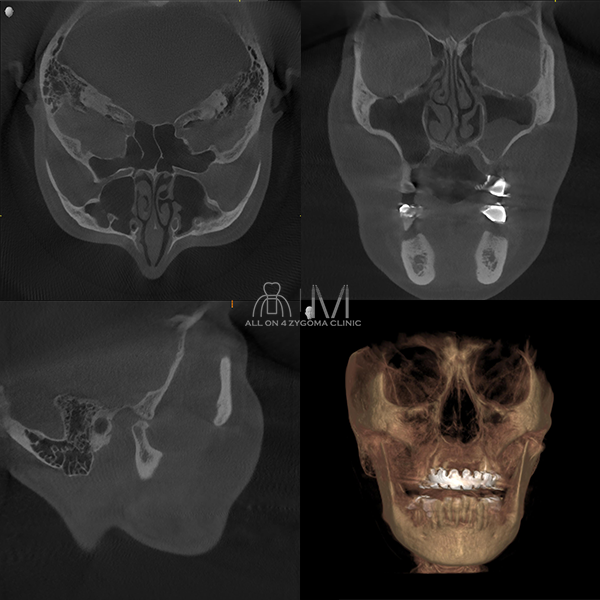

両側上顎は前臼歯歯槽骨に十分なボリュームがないが、頬側に十分なスペースの確保が見込めた。下顎は菲薄な部位はあるものの5┬5を骨整形する事で十分な骨幅の確保が見込めると判断し、この部位に4本ノーマルインプラント埋入予定とした。前歯~小臼歯部で歯槽堤の高低差が大きいことから、安定度を高めるプラットフォームの設計が必要であると考えた。また、頬骨に十分な厚みがある事からザイゴマインプラント4本を用いる上下顎All-on-4治療 を計画した。手術を円滑なものとする為、術中は静脈内鎮静法下での手術を予定した。